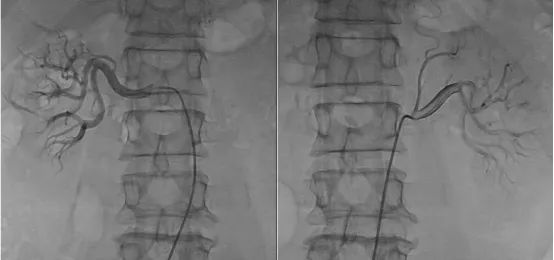

经过充分地评估、讨论并取得同意后,王政主任团队决定为付先生实施肾神经标测/选择性消融(msRDN)高血压微创介入手术。术中,王政主任根据标测结果筛选出真正需要消融的“热点”(电刺激后收缩压持续上升>5mmHg),并顺利对付先生双侧肾动脉的交感神经进行消融。消融后即刻再次电刺激验证消融效果(电刺激后观察血压是否下降),左侧肾动脉成功消融5个热点,右侧肾动脉成功消融6个热点。术后,复查造影显示付先生肾动脉血流正常,无明显血管损伤,术前血压146/103mmHg,术后监护血压115/73mmHg,手术圆满完成。